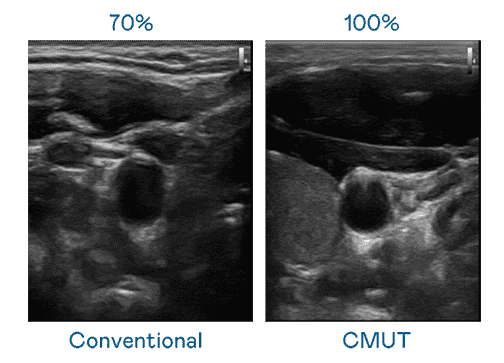

CMUT 技术是一种用电容式微机电元件来产生超音波讯号的技术。。。与传统 PZT 压电式技术相比,,CMUT 频宽增加 30%,,,,更宽频的超音波讯号让影像解析度大幅提升,,,是实现高影像品质医疗超音波扫描、、、促进精准医疗发展的关键技术。。。

大频宽带来超清晰影像

超音波影像的解析度高低,,首先取决于探头能发出的讯号频宽。。。冰球突破 CMUT 可提供高清晰的超音波讯号,,,,提供高频宽、、、高灵敏度、、影像纹理细节更高的超音波影像,,,,协助医护人员缩短影像判读时间及利用精准的医疗影像进行诊断。。